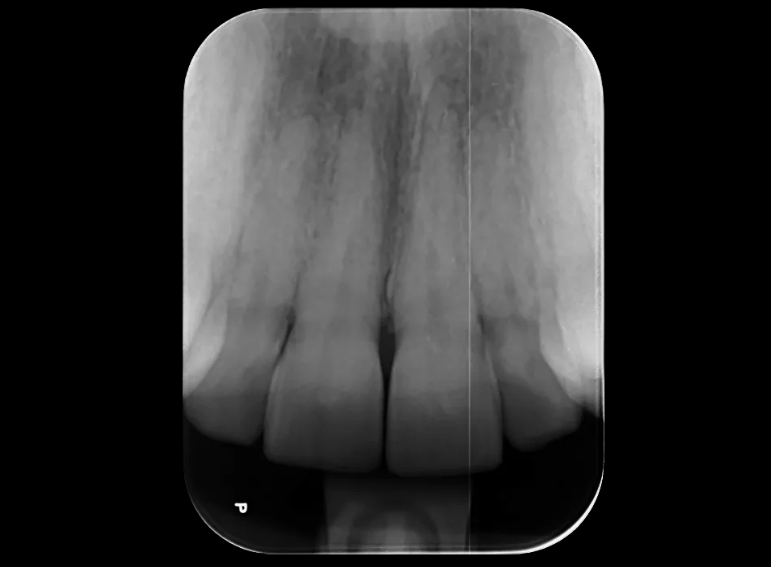

Root canal treatment and combined internal and external whitening.